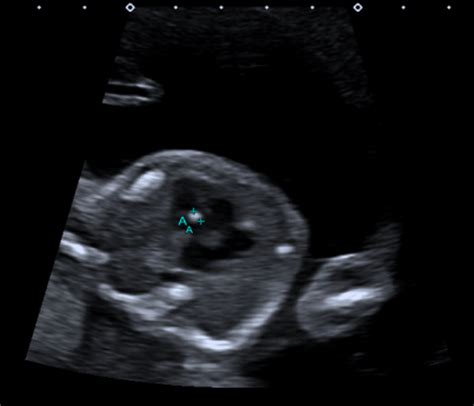

Alright, first things first: What exactly is this 20-week scan all about? In a nutshell, it’s a detailed ultrasound performed during the second trimester of pregnancy, typically between 18 and 22 weeks. This scan is super important because it provides a thorough check-up of your baby’s development. Think of it like a comprehensive health check for your little one before they make their grand entrance into the world. The sonographer, a trained professional, will use ultrasound waves to create images of your baby, allowing them to examine various aspects of their anatomy.

So, what exactly do they look for? The 20-week scan is a comprehensive assessment, covering a wide range of fetal structures and potential issues. The primary goal is to identify any structural abnormalities or birth defects. This includes checking the baby’s brain, spine, heart, kidneys, limbs, face, and other vital organs. They also assess the placenta, the amniotic fluid levels, and the umbilical cord to ensure everything is functioning correctly and supporting the baby’s growth. In India, like in many other countries, this scan is a standard part of prenatal care, giving parents and healthcare providers valuable insights into the baby’s health.

It’s important to remember that the 20-week scan is not foolproof. There are limitations to what ultrasound can detect. Some conditions might not be visible at this stage, and there’s a small chance of false positives or false negatives. However, the scan provides a wealth of information, and it’s a crucial part of prenatal care. The scan itself is painless. You’ll lie down on a table, and the sonographer will apply a gel to your abdomen to help the ultrasound probe glide smoothly. They’ll move the probe around to get different views of your baby. The process typically takes about 30 to 60 minutes, depending on the baby’s position and how clear the images are. So, relax and try to enjoy the first glimpses of your baby! Bring your partner or a friend to share the experience, and don’t hesitate to ask questions. It’s all about being informed and prepared!